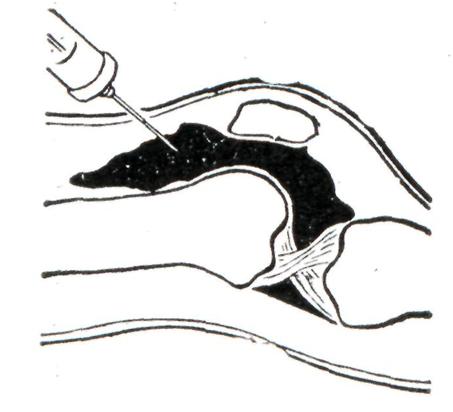

Один из важнейших диагностических методов, позволяющий установить наличие и активность процесса в суставе, — пунктирование сустава с извлечением и анализом синовиальной жидкости. Пониженная вязкость, плохой муциновый сгусток, увеличение количества лейкоцитов (до 50 000 в 1 мм3) говорят о воспалительном характере синовиальной жидкости. Качественная характеристика цитоза (например, преобладание нейтрофилов при ревматоидном артрите, лимфоцитов при туберкулезном), наличие кристаллов (например, мочевой кислоты при подагрическом артрите), иногда наличие инфекционных возбудителей в синовиальной жидкости позволяют установить точный диагноз болезни.

Местное лечение: иммобилизация конечности (гипсовые лонгеты, шины и другое), при наличии значительного количества гнойного выпота периодические пункции сустава (рис. 19) с эвакуацией гнойного экссудата и промыванием полости сустава растворами антисептиков. Первая пункция сустава заканчивается введением антибиотиков широкого спектра действия, при всех последующих пункциях используются антибиотики с учетом чувствительности микрофлоры к ним; частота подобной санации полости сустава зависит от темпов накопления и количества вновь образующегося выпота. Пункции прекращают, когда выпот приобретает серозный характер и количество его становится незначительным. Иногда после первой пункции в полости сустава оставляют ниппельный дренаж.

Рис. 19. | ||